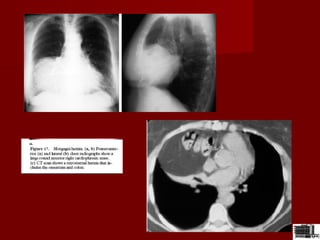

Masa mediastinala?Masa mediastinala?

Aorta ectaziata alungitaAorta ectaziata alungita

Ectazie si alungire de trunchiEctazie si alungire de trunchi

brahiocefalicbrahiocefalic

 Radiologic:proeminenta pe marginea dreapta aRadiologic:proeminenta pe marginea dreapta a

mediastinuluimediastinului

 pacienti in virstapacienti in virsta

 ateromatosiateromatosi

 hipertensivihipertensivi